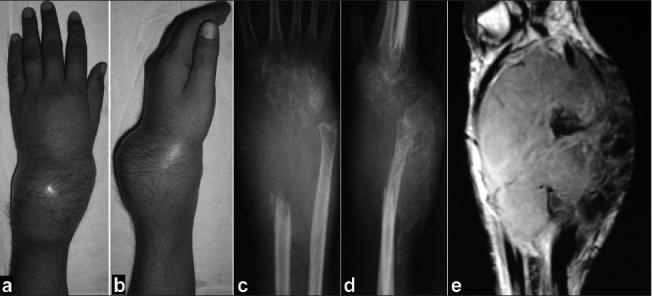

Giant cell tumor (GCT) of the distal radius poses problems for reconstruction after resection. Several reconstructive procedures like vascularized and non-vascularized fibular graft, osteo-articular allograft, ceramic prosthesis and megaprosthesis are in use for substitution of the defect in the distal radius following resection. Most authors advocate wrist arthrodesis following resection of distal radius and non vascularized fibular graft. Here we have analyzed the results of aggressive benign GCTs of the distal radius treated by resection and reconstruction arthroplasty using autogenous non-vascularized fibular graft.

Twenty-four cases of giant cell tumor of the distal radius (mean age 32 years, mean follow-up 6.6 years) treated by en-bloc resection and reconstruction arthroplasty using autogenous non-vascularized ipsilateral fibular graft with a minimum followup of two years have been included in this retrospective study. Nineteen cases were of Campanacci grade III and five were of Grade II recurrence. The mean resected length of the radius was 9.5 (8-12) cm. Routine radiographs and clinical assessments regarding pain, instability, recurrence, hand grip strength and functional status were done at regular intervals and functional results were assessed using (musculoskeletal tumor society) MSTS-87 scoring.

Early radiological union at host-graft junction was achieved at mean 12.5 weeks, (range 12-14 weeks) and solid incorporation with callus formation was observed in mean 29 weeks (range 28-32 weeks) in all the cases. Satisfactory range of motion (mean 63%, range 52-78%) of the wrist was achieved in 18 cases. Grip strength compared to the contralateral hand was found to be 67% (range 58-74%). Functional results were excellent in six cases (25%), good in 14 cases (58.3%) and four (16.7%) cases had fair results. Soft tissue recurrence was seen in one patient. The most commonly encountered complication was fibulo-carpal subluxation (10 cases, 41.7%).

Resection of the distal radius and reconstruction arthroplasty with non-vascularized proximal fibular graft is useful in preserving the functional movement and stability of the wrist as well as achieving satisfactory range of movement and grip strength.